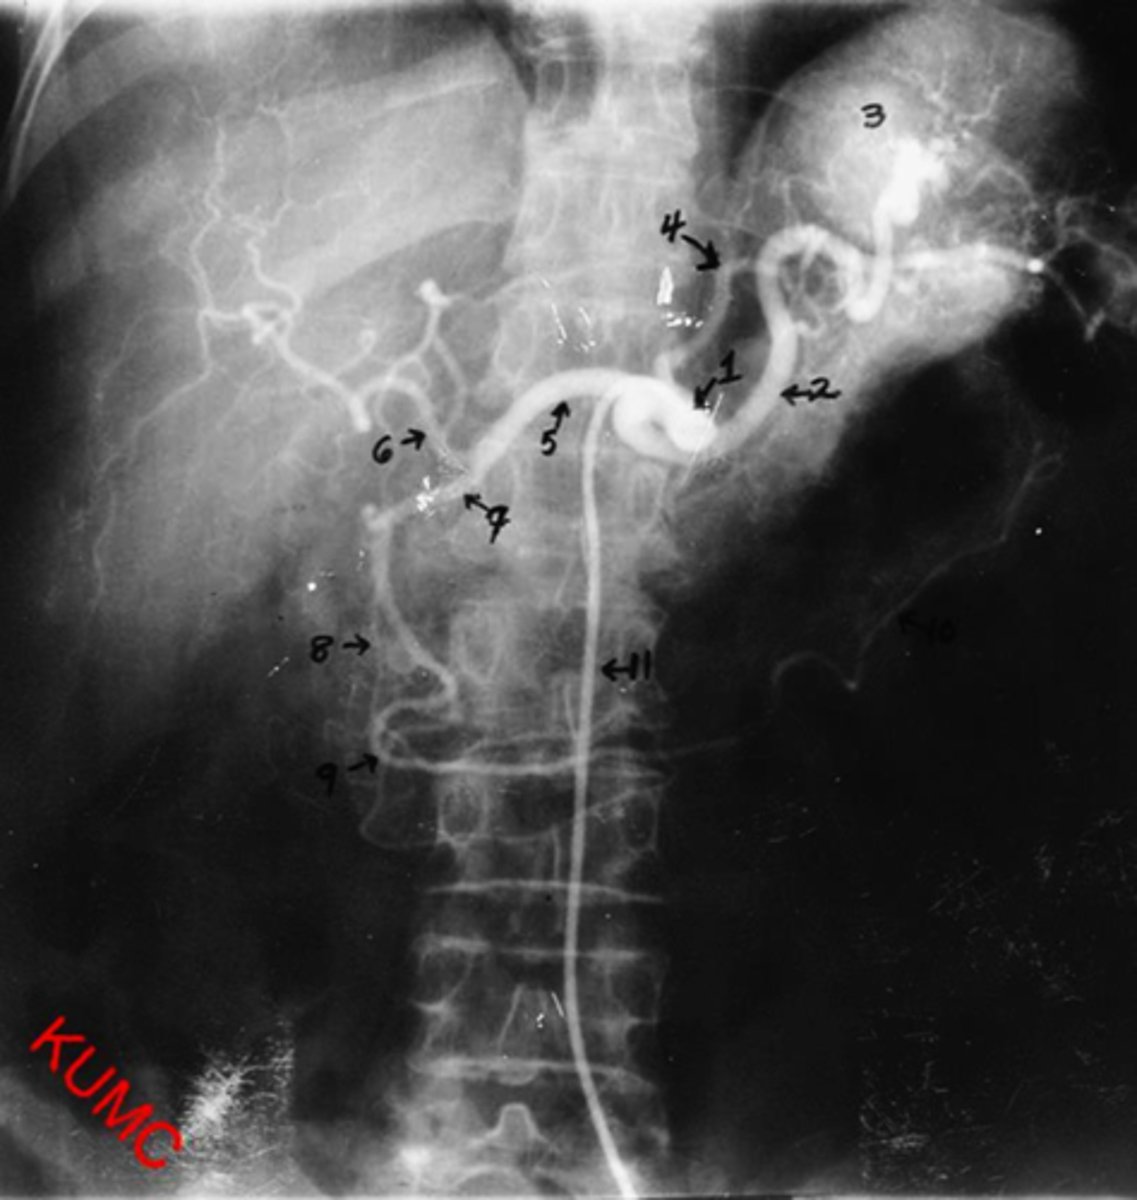

Identify indicated anatomy in the following radiograph

1.Right hepatic duct

2.Left hepatic duct

3.Common hepatic duct

4.Gallbladder

5.Cystic duct

6.Common bile duct

7.Pancreatic duct

8.Spinous process

<p>1.Right hepatic duct</p><p>2.Left hepatic duct</p><p>3.Common hepatic duct</p><p>4.Gallbladder</p><p>5.Cystic duct</p><p>6.Common bile duct</p><p>7.Pancreatic duct</p><p>8.Spinous process</p>